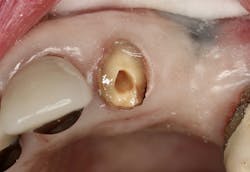

Figure 2: Intaglio surface of existing PFM retrofit preparation

The intaglio surface of the PFM crown contained the preexisting dentin core preparation. The decision was made to prepare the surface to receive the intraoral portion of the post rather than completely remove the remaining dentin (figure 2). This was done to facilitate a smooth retrofit between the remaining root structure and intaglio crown surface as well as to maximize bonding surface area between segments.